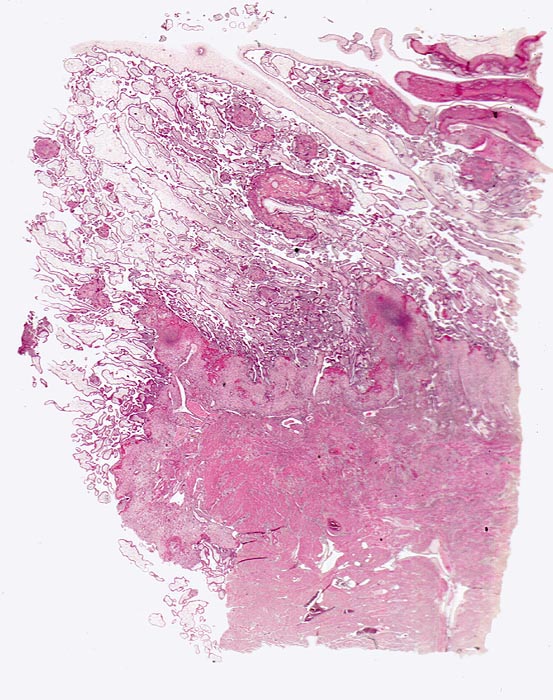

Morphologische Merkmale:

• Myometrium bedeckt von dezidualisiertem Endometriumstroma der Dezidua basalis.

• Invasion des Myometriums durch intermediären extravillösen Trophoblast.

• Fibrinoidschicht.

• Chorionzotten, ein Teil davon verankert mit dem dezidual transformierten Endometrium = Dezidua basalis (Haftzotten).

• Choriondeckplatte.

• Rechts oben Anteile des Chorion laeve.